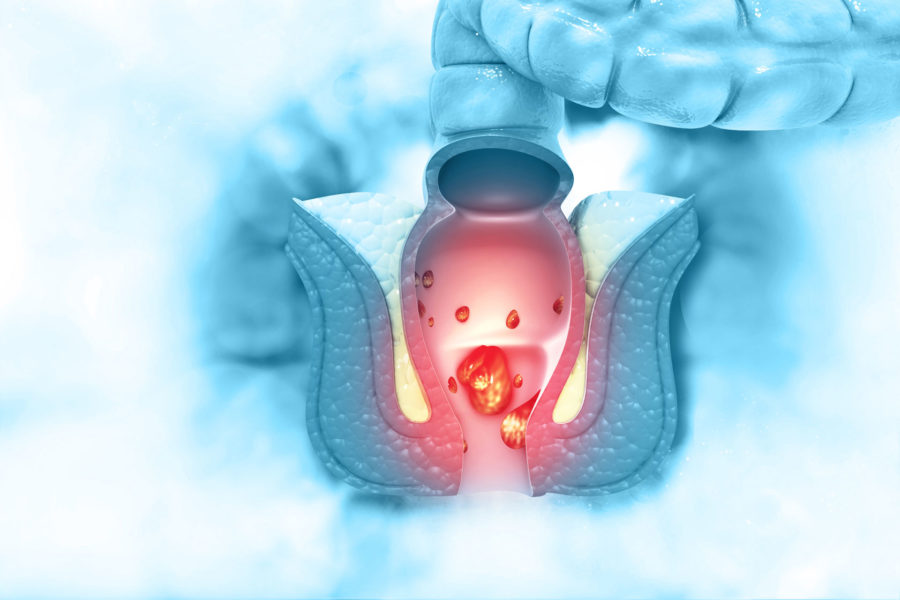

Der Darmkrebs (Karzinom) ist eine der häufigsten Tumorerkrankungen. Dabei wird zwischen Dickdarmkrebs (Kolonkarzinom) und Mastdarmkrebs (Rektumkarzinom) unterschieden.

Bei den Karzinomen, die den Mastdarm betreffen, führt, in Abhängigkeit von der Größenausdehnung des Tumors, eine Vorbehandlung mit einer Kombination aus Bestrahlung und Chemotherapie mit anschließender Operation zum optimalen Therapieerfolg.

Bei allen operativen Verfahren wenden wir die gewebeschonende minimalinvasive Methode an. Das bedeutet weniger Wundschmerz, kleinere Narben und schnellere Genesung. Dabei werden wir versuchen, wenn immer es möglich ist, einen Seitenausgang (Anus präter = Stoma) zu vermeiden.